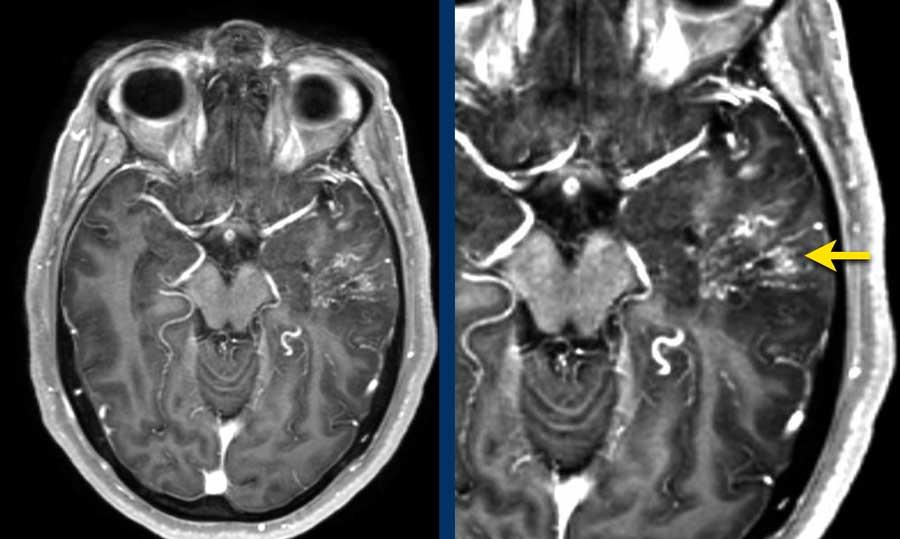

Bệnh nhân nam 65 tuổi với triệu chứng đau đầu khởi phát đột ngột.

NCCT cho thấy xuất huyết dưới nhện hai bên và xuất huyết nhu mô não (mũi tên vàng).

CTA cho thấy tại vị trí xuất huyết nhu mô có một túi phình liên quan đến dòng chảy của động mạch thông trước, được xem là nguyên nhân gây xuất huyết dưới nhện.

Lưu ý khối xuất huyết bên cạnh túi phình (vòng tròn).

CTA cũng cho thấy một AVM với nidus ở thùy trán trái (mũi tên xanh lá).

Ở bệnh nhân có AVM, huyết động học có thể thay đổi theo cách làm suy yếu thành động mạch và dẫn đến hình thành túi phình.

Hình CTA nhìn nghiêng:

- Túi phình liên quan đến dòng chảy kèm túi phình con tại đáy túi phình – mũi tên vàng

- Động mạch nuôi – mũi tên xanh lá

- Nidus AVM – vòng tròn

- Tĩnh mạch dẫn lưu giãn – mũi tên xanh dương

Hình bên trái: DSA túi phình trước điều trị.

Hình bên phải: DSA sau điều trị bằng đặt coil riêng biệt cho túi phình chính và túi phình con (mũi tên vàng).

Quyết định điều trị túi phình trước và phẫu thuật cắt bỏ AVM trong giai đoạn bán cấp khi bệnh nhân đã hồi phục sau xuất huyết dưới nhện.